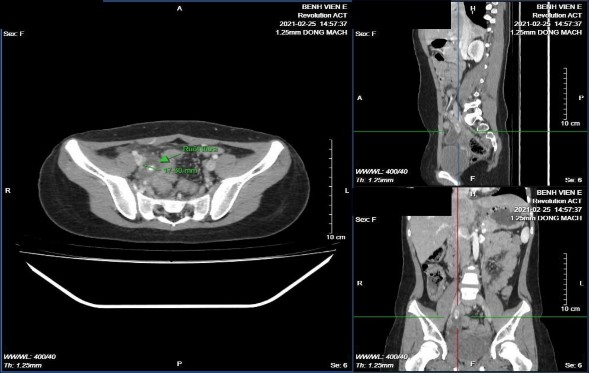

Hình 3.4: Ruột thừa nằm ở vị trí tiểu khung, trong lòng có sỏi phân.

BN Chu Tuệ M. 10 tuổi, mã bệnh án 2104324. Phẫu thuật thấy ruột thừa chạy chếch xuống tiểu khung, kết quả giải phẫu bệnh ruột thừa viêm mủ.